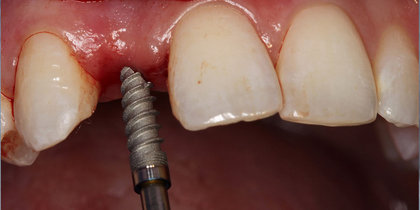

• A central incisor is extracted and immediately replaced with a Glidewell HT Implant and provisional crown, facilitating an esthetic final outcome. thumbnail image

Immediate Provisionalization

A central incisor is extracted and immediately replaced with a Glidewell HT Implant and provisional crown, facilitating an esthetic final outcome.